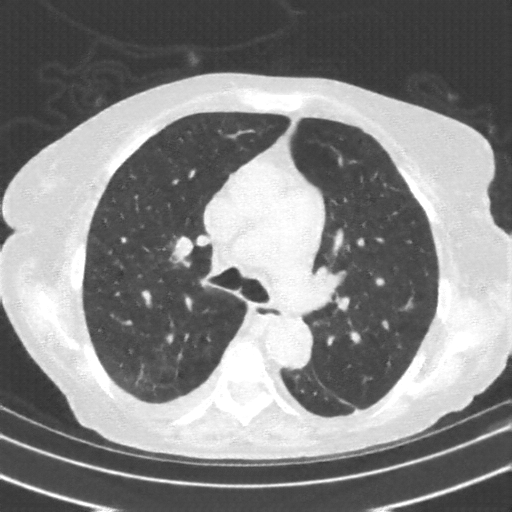

Targeted Slice 70 - Lung Window Analysis (Generated vs Real Venous)

0.583

Lung SSIM

161.5

Lung RMSE

72.4

Lung MAE

Average Lung Window Metrics Across All Slices (153 slices) - Generated vs Real Venous

0.553

Lung SSIM (Avg)

147.1

Lung RMSE (Avg)

69.0

Lung MAE (Avg)

Original VENOUS CT scan

Lung window (WL -600, WW 1500 β†’ Low βˆ’1350, High +150)